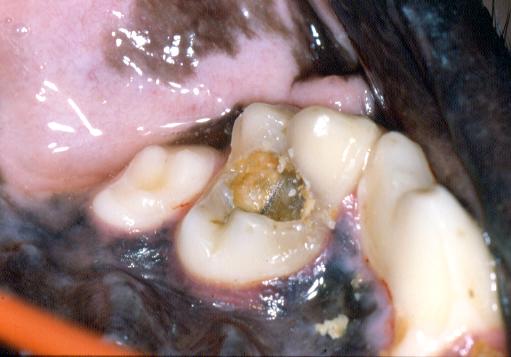

Teeth Destroyed by Disease

Teeth ruined by advanced caries, feline neck lesions etc.

should be considered for extraction.

Advanced feline odontoclastic resorptive lesion on buccal

surfaces of 409 and 407